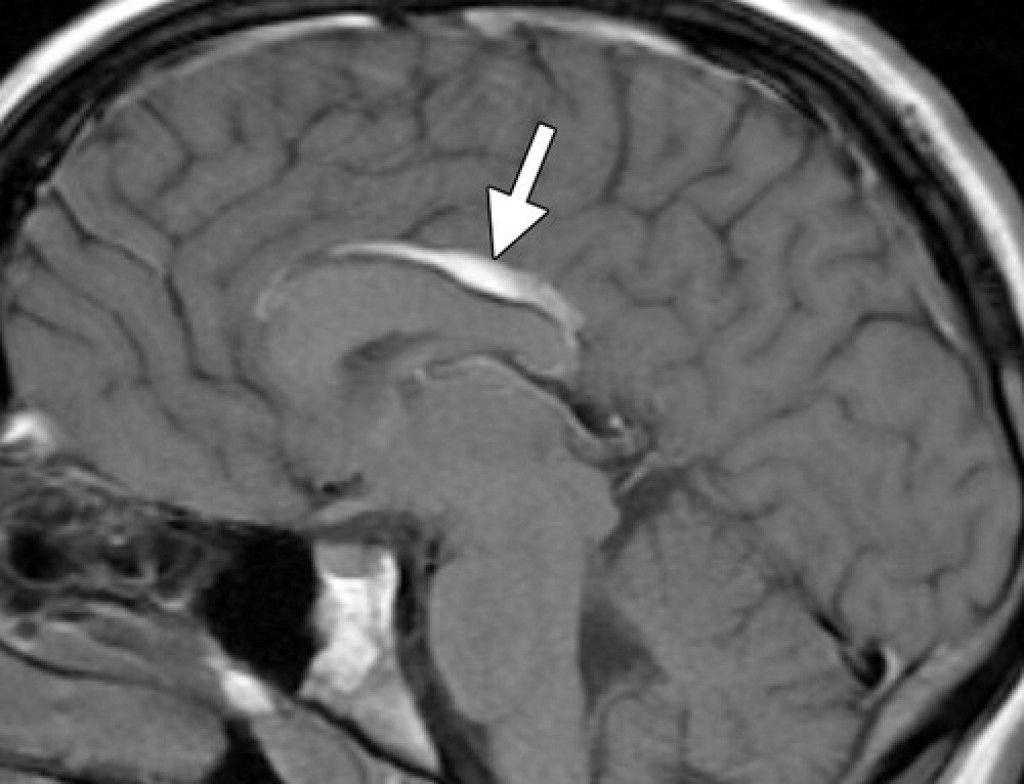

Внутричерепная гипотензия: КТ-исследования и их интерпретация

Раздел: Образы вокруг